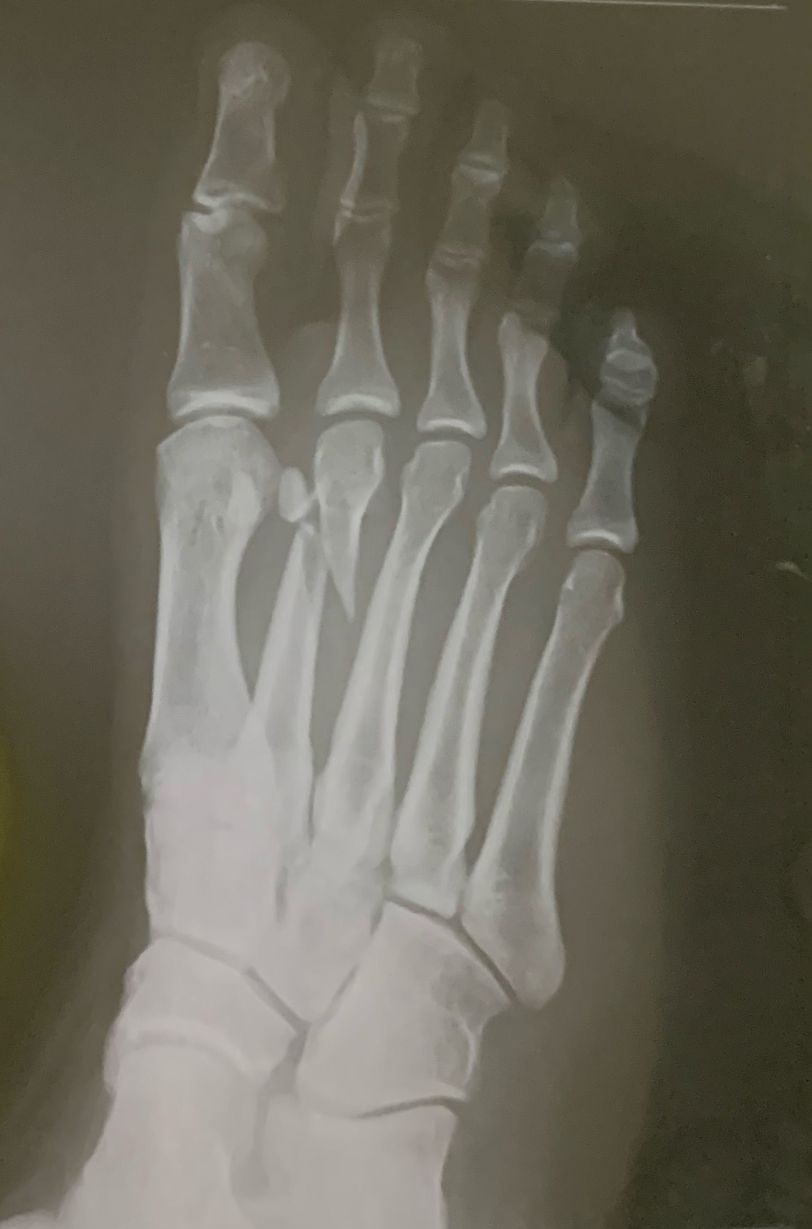

X-ray

What is the diagnosis

Fracture of the 2nd metatarsal bone

First of all support #back-slab